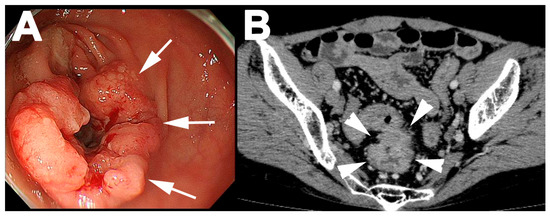

2. Case Report